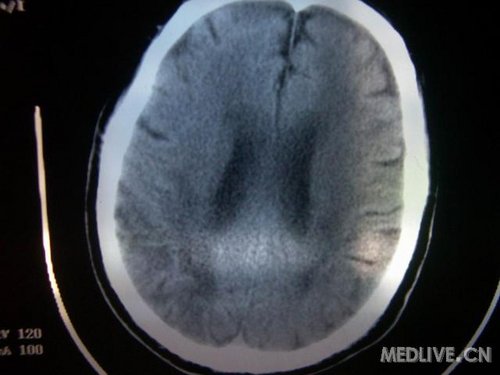

病人男性 73岁 市民 以“幻听、幻视两天,言语含糊、精神错乱一天”入院。

两天前无诱因出现幻听、幻视,描素眼前有彩色的圆圈,听见有人说话(但说什么不详),一天前出现胡言乱语,言语含糊,精神错乱,问话不答,行走略有不稳,来我院就诊,门诊头CT检查:(下面有片)入院后查体不合作,表情淡漠,问话不答,大致检查了一下,颅神经未见明显异常,颈软,右手活动似忽略差。其他检查不配合。脑电图:广泛轻-中度异常。

既往史:半年前曾患“右侧脑梗塞”但无明显后遗症,生活能自理,无高血压、糖尿病、心脏病史。

此次入院时的片子: